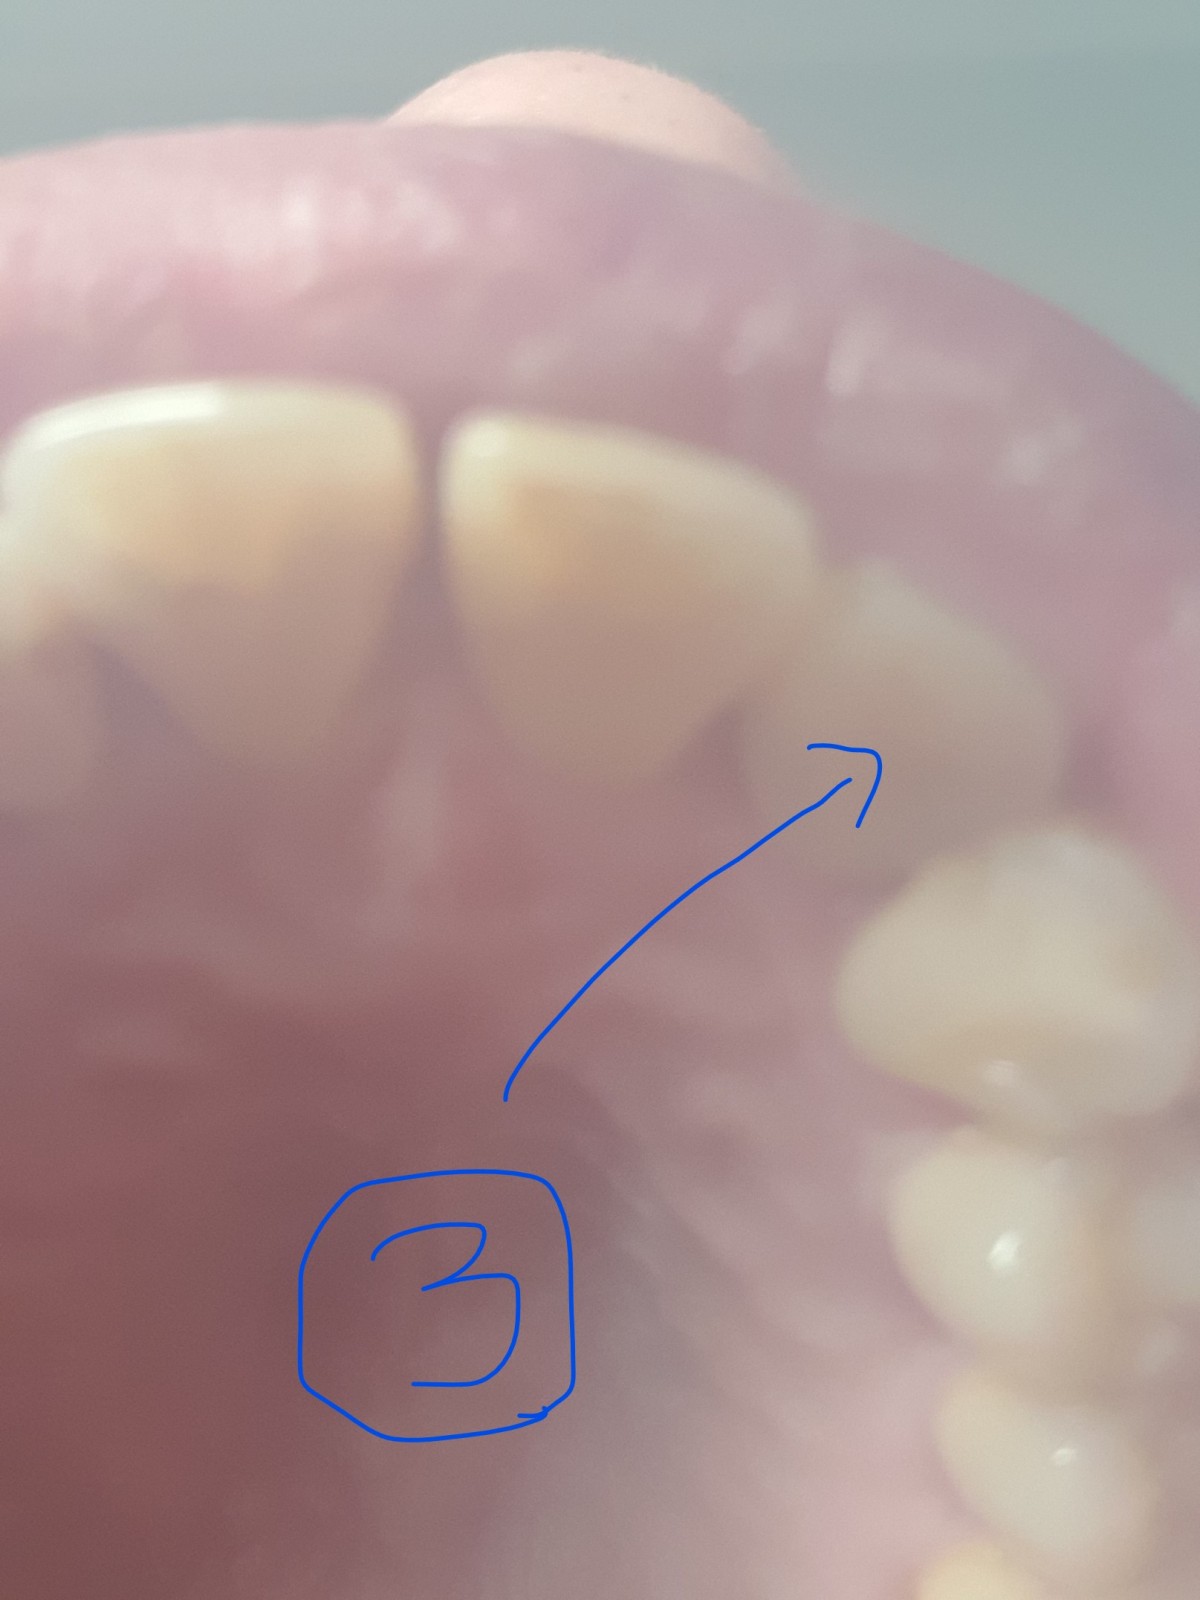

교합이 되는데 저 교합은 한단계 더 깊은 교합전에 중간에 상악 12번 레진 안쪽 첨부된 사진 숫자 3번으로

표시한 부분처럼 레진 안쪽이 다른 주변이 보다 상대적으로 두껍다라는 느낌이 있습니다. 두께 때문에

안쪽 1/4지점에서 아래니가 걸린다 느낌이고 특히 정자세로 누웠을때 그 느낌을 더 강하게 옵니다.